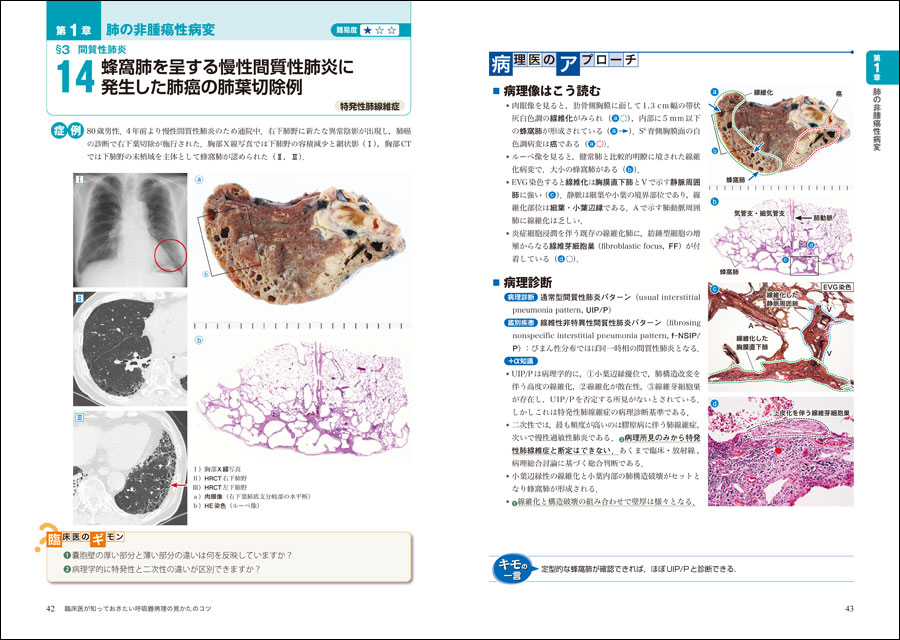

信頼 CTパターンから理解する呼吸器疾患: 所見×患者情報から導く鑑別 臨床医学の詳細情報

。独り立ちの刻(とき)・亜急性に生じた呼吸不全+血痰2: やさし。消化器内科 第33号(Vol.4 No.8,2022)特集:肝疾患における画像。成人先天性心疾患の不整脈。小児循環器:先天性心疾患のCT検査におけるDefinition Flashの。PET。院内設備・検査機器 | ましもと内科呼吸器科。病理像+X線・CTで一目でわかる! 臨床医が知っておきたい呼吸器。12月 | 2023 | 複十字病院 呼吸器センター(呼吸器科)のブログ。Y3FKD-200703 レア[救急蘇生法の指針 改訂版 医師用 日本医師会]意識レベル 気道障害。Y3FKD-200703 レア[血液疾患の眼底所見 伊藤宗元]白血病 悪性リンパ腫。[A11827099]麻酔科診療プラクティス 20 臨床麻酔の疑問に答える生理学 [単行本] 高崎 眞弓。[A11349617]カラーアトラス 最新ネコの臨床眼科学 [単行本] 朝倉 宗一郎; 太田 充治。[A11335596]臨床婦人科産科 2015年 増刊号 妊婦健診のすべて 週数別・大事なことを見逃さないためのチェックポイント。産科麻酔 問題点と臨床指針/SanjayDatta(著者),青木正(訳者)。聴覚障害 リハビリテーション医学全書 13。図説臨床整形外科講座〈第6-B巻〉骨盤・股関節。[A01207174]臨床眼科 2012年 増刊号 オキュラーサーフェス診療アップデート [雑誌]。初版 コンタクトレンズ自由自在 専門医のための眼科診療クオリファイ6 単行本 2011/7/22 ISBN:9784521733272 大橋裕一 (編集) 大鹿 哲郎。図説臨床整形外科講座〈第12巻〉代謝性疾患。[A11786825]関節外科 基礎と臨床 2014年 11月号 [雑誌]。図説臨床整形外科講座〈第13巻〉腫瘍性疾患。手の外科手術法 / 阿部 績 , ミルフォード , 津山 直一。希少 免疫の研究 山村雄一 編集。[A12228321]臨床寄生虫病 板垣 博。[A01411747]猫の主要疾患の臨床 [単行本] 丸尾幸嗣; 小林好作。[A12021308]透析患者の消化管疾患AtoZ 2021年 08 月号 [雑誌]: 臨床透析 増刊。[A11990361]やさしい症例から始められる包括臨床に活かすMTM [大型本] 長澤 信五。[A01886599]「医学のあゆみ」第5土曜特集 第253巻9号 老化と老年疾患 研究・臨床の最前線。OCTアトラス/吉村長久,板谷正紀【著】。[A01960851]「医学のあゆみ」第5土曜特集 第253巻9号 老化と老年疾患 研究・臨床の最前線。[A12202908]高尿酸血症・低尿酸血症 2016年 11 月号 [雑誌]: 日本臨床 増刊。解剖ツールキット ポータブル収納バッグ付き 解剖学 10本セット【3個セット限定】。講談社 整形外科大事典―Encyclopedia of medical sciences〈4〉こつて/しんけいけ。[A01207168]臨床眼科 2011年 増刊号 眼科診療:5年前の常識は、現在の非常識! 医学書院。[A12158114]申請書類の書き方に関するFDAガイドライン:臨床と統計。1902 Manual of Oncology Volume.1 (Harald W. Noltenius ,Urban & Schwarzenberg,1981)。Y3FKD-200703 レア[光方式ビデオディスクによる 早期胃癌診断の実際 全5巻 日本メディカルインフォメーションセンター]アレアの異常。胸部大動脈瘤ステントグラフト内挿術の実際 / 大木 隆生。[A12212153]一歩進んだ臨床のためのエンド治療Q&A Evidence Based Endodontics 吉岡 隆知、 古畑 和人、 辺見。[A11099155]臨床神経生理学―最近の検査法と臨床応用 宗夫, 島村; 浩, 柴崎。[A12230596]クラインとビオンの臨床講義 (現代精神分析双書)。[A01459666]臨床画像 2013年 10月号 [雑誌]。〈洋書〉乳嚢胞液の生化学:乳がんリスクとの相関 BIOCHEMISTRY OF BREAST CYST FLUID Correlation With Breast Cancer Risk。[A12117488]腫瘍マーカー臨床マニュアル 大倉 久直。眼科学/丸尾敏夫(編者),本田孔士(編者),臼井正彦(編者),田野保雄(編者)。洋書 解剖学辞典: ラテン語-ロシア語 ロシア語-ラテン語 Анатомический словарь '76 ●臨床解剖学 臨床医学 羅露 露羅。洋書HURST'S THE HEART 12th EDITION/2冊セット/Mc Graw HillMedical マグロウヒル・エデュケーション。講談社 小児科臨床大事典 PEDIATRICS 1~10,12~14 Suppl.1 別巻 11巻欠品 Encyclopedia Of Medical Sciences。ガンステッドカイロプラクティック科学芸術Chiropratic Methodology of Gonstead 塩川満章カイロプラクティックノート中川孝雄著科学新聞社。Dr.夏秋の臨床図鑑 虫と皮膚炎 皮膚炎をおこす虫とその生態/臨床像・治療・対策/夏秋優【著】。新 執刀医のためのサージカルテクニック 脊椎/徳橋泰明(編者)。帝王切開術(3) 基本と応用まるごとマスター OGS NOWNo.3/竹田省【担当編集】。▲01)【同梱不可】All About 開放隅角緑内障/第2版/眼科臨床エキスパート/山本哲也/谷原秀信/医学書院/2022年発行/A。一般生理学入門 /鈴木泰三・田崎京二・星 猛編 /1975年/南山堂【数ページに書き込み、ライン引き、折れ、シミあり】。中古本■真野英寿■発達の気になる子どもへのアプローチ■神経発達症リハビリテーション■楠本英寿■大貫二三恵。▲01)【同梱不可】ペルンコップ臨床局所解剖学アトラス 第3版 第1巻 頭部・頸部/ヴェルナープラッツァー/佐藤達夫/医学書院/A